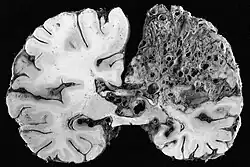

Neuropathology

Neuropathology is the study of disease of nervous system tissue, usually in the form of either surgical biopsies or sometimes whole brains in the case of autopsy. Neuropathology is a subspecialty of anatomic pathology, neurology, and neurosurgery. In many English-speaking countries, neuropathology is considered a subfield of anatomical pathology. A physician who specializes in neuropathology, usually by completing a fellowship after a residency in anatomical or general pathology, is called a neuropathologist. In day-to-day clinical practice, a neuropathologist generates diagnoses for patients. If a disease of the nervous system is suspected, and the diagnosis cannot be made by less invasive methods, a biopsy of nervous tissue is taken from the brain or spinal cord to aid in diagnosis. Biopsy is usually requested after a mass is detected by medical imaging. With autopsies, the principal work of the neuropathologist is to help in the post-mortem diagnosis of various conditions that affect the central nervous system. Biopsies can also consist of the skin. Epidermal nerve fiber density testing (ENFD) is a more recently developed neuropathology test in which a punch skin biopsy is taken to identify small fiber neuropathies by analyzing the nerve fibers of the skin. This test is becoming available in select labs as well as many universities; it replaces the traditional nerve biopsy test as less invasive.